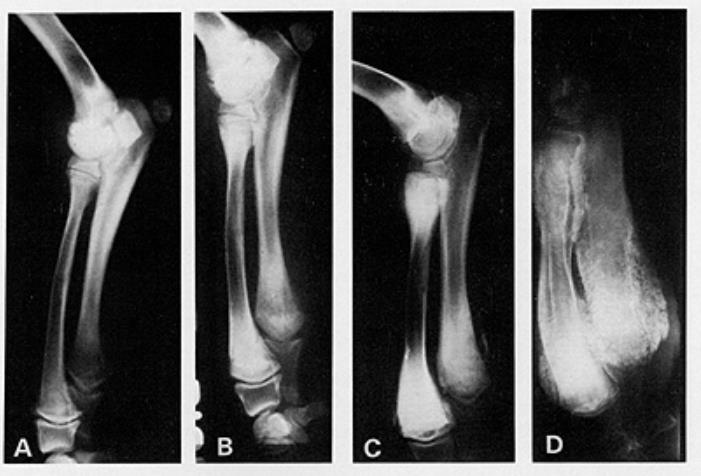

X光线通常显示病变骨头的变化,例如与生长板平行线的外观,骨密度的变化以及生长板周围的钙化。

肥大性骨营养不良也称为骨骼坏血病,Barlow氏病或Moller-Barlow氏病。最早是在1930年代中期的文献记载中出现。发病部位通常集中在桡骨、尺骨周围的生长板和胫骨等长骨的干骺端。尽管它主要只影响前两条腿,但也有可能发生在爪子,肋骨和下颌中。

大部分小狗都可以恢复得很好,生长板闭合后很少出现复发情况。但如果病龄过长没有得到治疗,那么小狗可能会出现手脚永久性弯曲畸形。